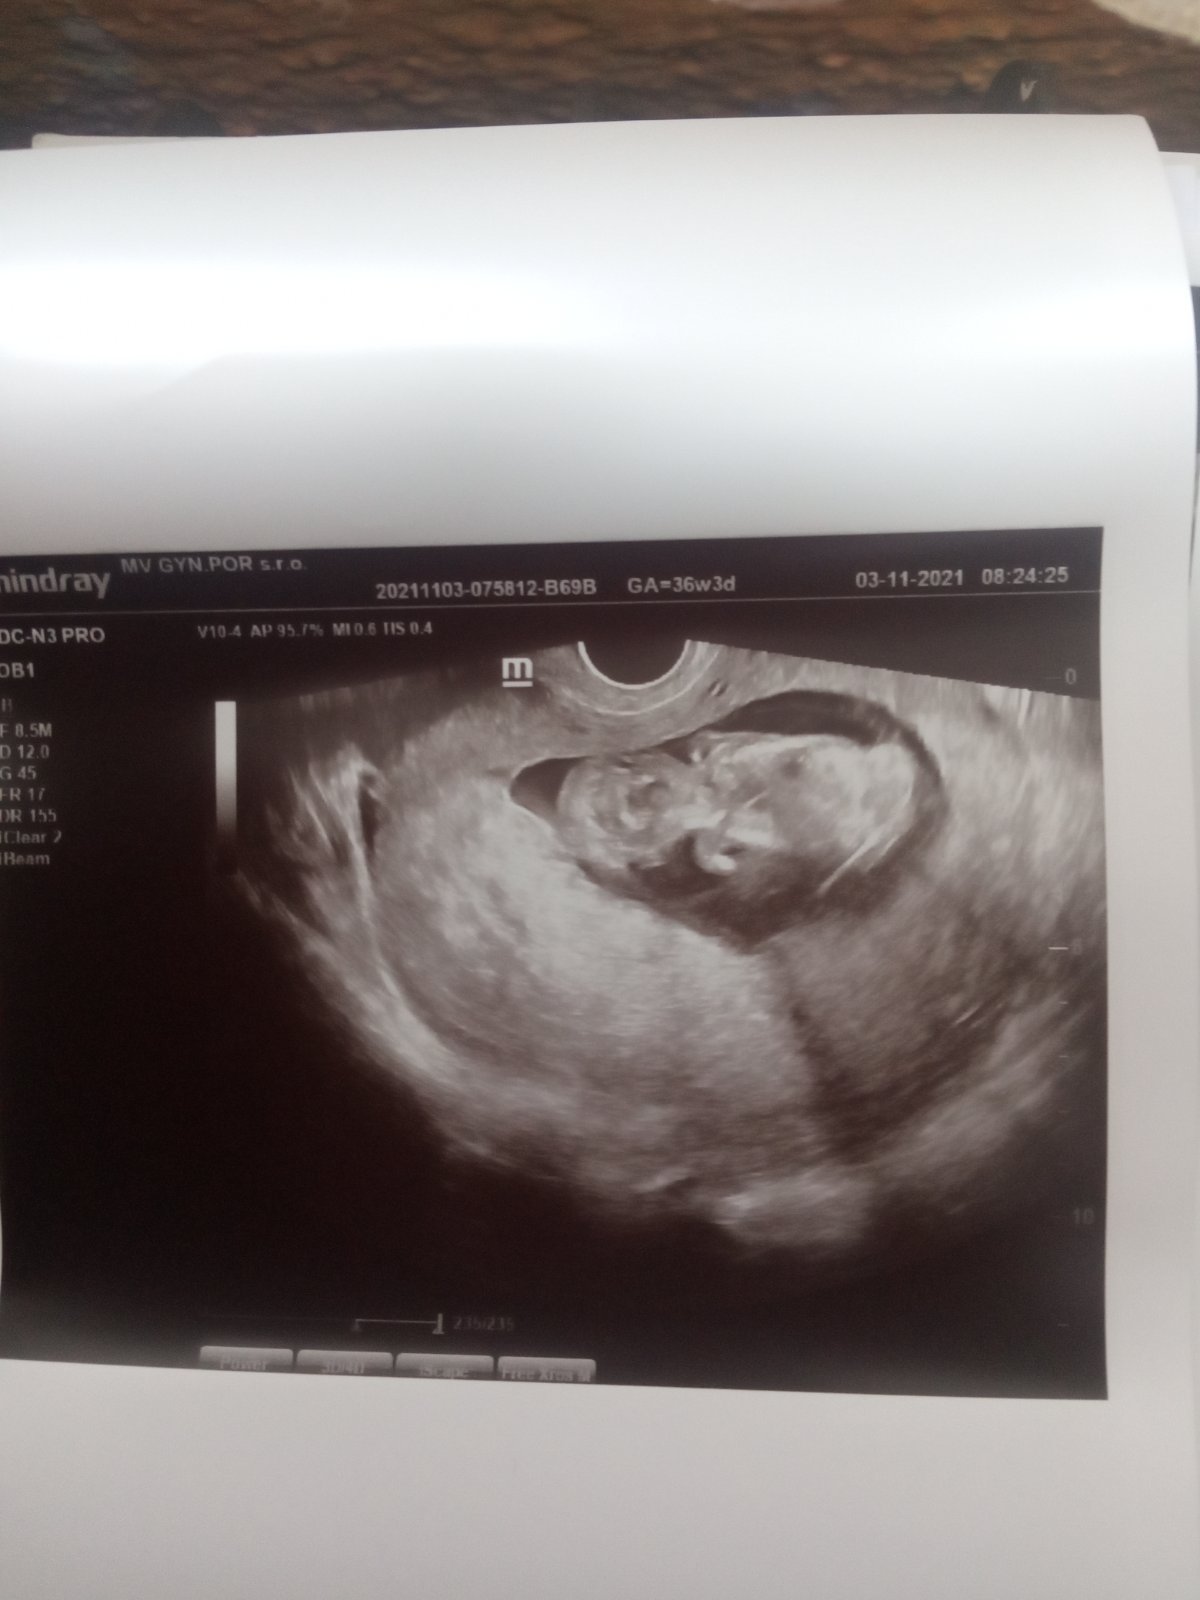

Bábo v 14. týždni